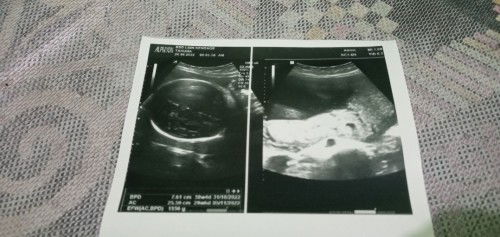

https://id.theasianparent.com/cara-membaca-hasil-usg baca link ini bun semoga membantu

brapa minggu ini bunda?